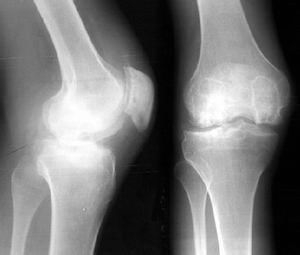

O型腿治疗前